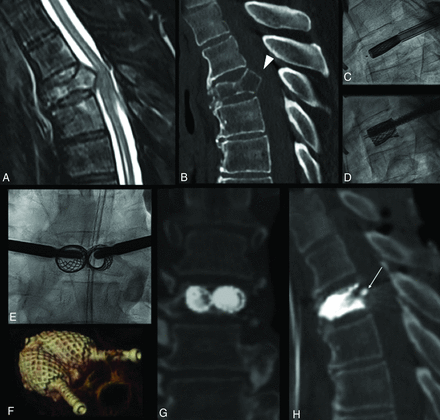

Severe L3 vertebral body collapse (A) in a 74-year-old woman with osteopenia following minor trauma. Intraoperative myelogram through intradural injection of contrast agent at L1–L2 (arrow, A) shows an opacification defect of the dural sac dorsal to the retropusled fragment at L3 (arrowhead, A). On fracture reduction through balloon-expanded vertebral body stents (B), the myelogram shows greater opacification of the dural sac at L3 (arrowhead, B), a real-time indirect sign of ligamentotaxis and partial central canal clearance. C and D, Preoperative and postoperative midsagittal CT images used for measurement of vertebral body height at the maximum point of collapse (red arrows) and of posterior wall retropulsion (white arrows) perpendicular to the dashed white line connecting the postero-inferior corner of the cranial vertebral body and the postero-superior corner of the caudal one, representing the expected original posterior wall, now intersecting the PWR.

PWR and VBH were measured on pre- and postprocedural CT scans by 2 readers, a neuroradiologist and a neurosurgeon, in consensus. Images were reformatted with orthogonal multiplanar reconstructions, with a section thickness of 2 mm, interval of 2 mm, and bone algorithm, on a PACS system. A straight line was drawn on the midsagittal plane from the posterior-inferior corner of the cranial to the posterior-superior corner of the caudal adjacent vertebral bodies, ideally representing the original position of the normal prefracture posterior wall of the target level. This line intersected the retropulsed fractured posterior wall. The PWR was then measured perpendicularly from this posterior wall line on the midsagittal image (Fig 1). VBH measurement was obtained on the midsagittal image from the superior-to-inferior endplates at the most collapsed point (Fig 1).

AKP was performed with VBS at 46/53 levels and with SJ at 7/53 levels. VBS AKP was performed with the SAIF technique at 33/46 levels. Intraoperative lumbar myelography was performed in 4 cases (Fig 1).

AKP can effect VBH restoration, avoiding height loss due to deflation effect, and is increasingly used as a stand-alone measure to reconstruct and restore axial-load capability in traumatic, osteoporotic, and malignant fractures.26,35 As a consequence of the internal fracture distraction and kyphosis reduction, AKP appears to allow ligamentotaxis correction of the PWR without the need to perform external distraction through a posterior instrumentation or even more invasive maneuvers of fragment repositioning through direct impaction. In this study, we included 8 neoplastic fractures that had a retropulsed bone fragment (Fig 2), while we did not include cases with epidural nonosseous soft-tissue masses. An epidural soft-tissue mass might, in fact, behave differently from an osseous PWR and would have been more difficult to measure on postoperative CT. Intraoperative myelography, already described in the setting of vertebral augmentation procedures at risk for central canal encroachment,36 was used in only a minority of cases in this series, but it seemed potentially useful in selected patients to have a visual control under fluoroscopy of the PWR and to directly demonstrate the effect of ligamentotaxis during fracture reduction (Fig 1).